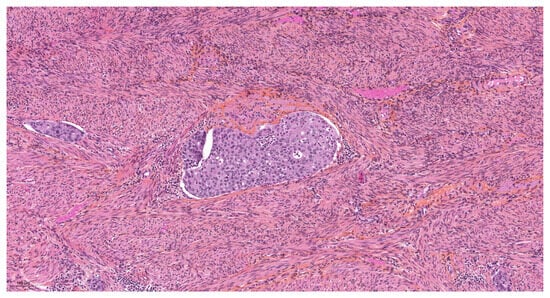

Artefacts in Hysterectomies with a Special Focus on Vascular Pseudoinvasion

| True vascular emboli | |

| Present | 11 (18.3) |

| Absent | 49 (81.7) |